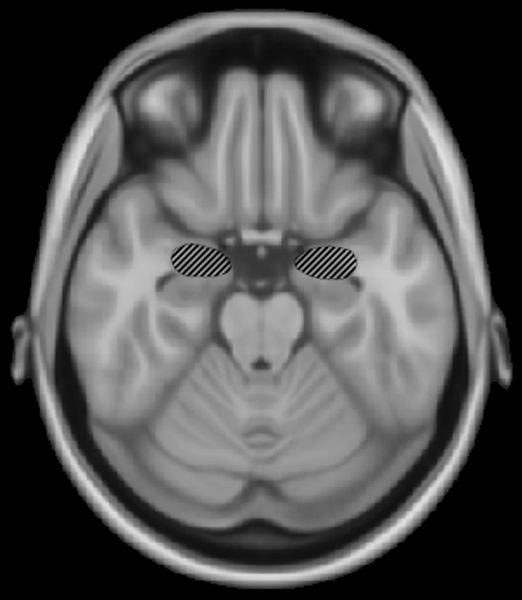

In a new paper published in the current issue of Neuron, Harvard Medical School researchers at McLean Hospital report that increased activity in the medial prefrontal cortex of the brain is linked to decreased activity in the amygdala, the portion of the brain where memories of frightening events are created.

Bolshakov and his colleagues tested their theory in mice. Divided into two groups, some were taught to fear an auditory stimulus while others were taught fear but had that memory extinguished. In the animals whose fear was extinguished, increased activation of the medial prefrontal cortex led to inhibition of the amygdala and significant decreases in fear responses.

“For example, if a sound ended with an extremely loud shriek, a subject would come to expect that scary noise at the end of the sound,” explained Bolshakov. “What we found was when we suppressed the fear memory by decreasing activity in the amygdala, the subjects were not afraid of the end of the auditory stimulus any longer.”